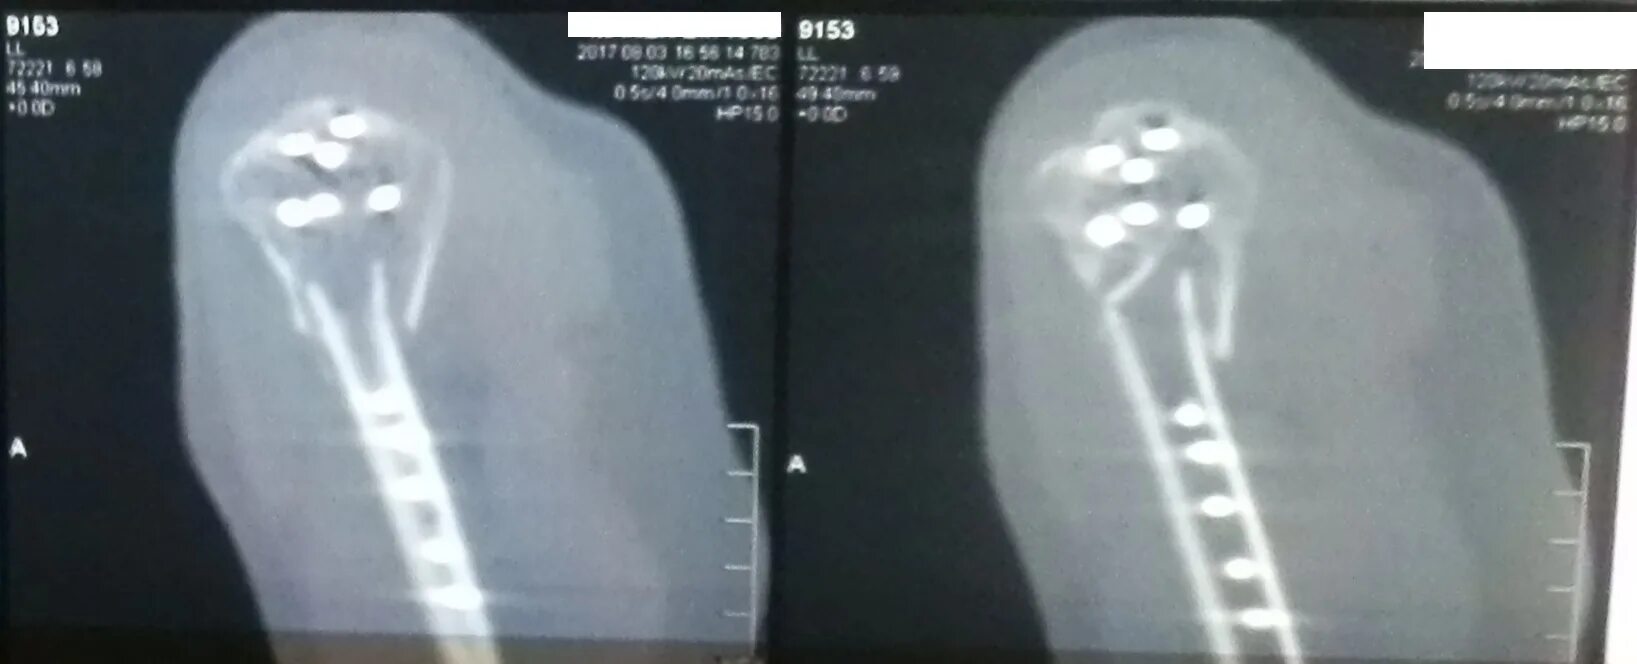

Перелом шейки плеча у пожилых